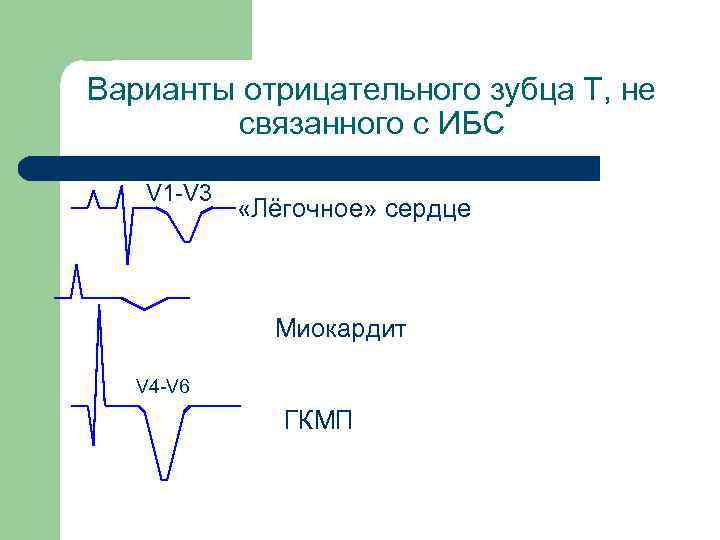

Инверсия зубца Т «Болезней много, а зубец Т один» Л. И. Фогельсон

Варианты отрицательного зубца Т, не связанного с ИБС V 1 -V 3 «Лёгочное» сердце Миокардит V 4 -V 6 ГКМП